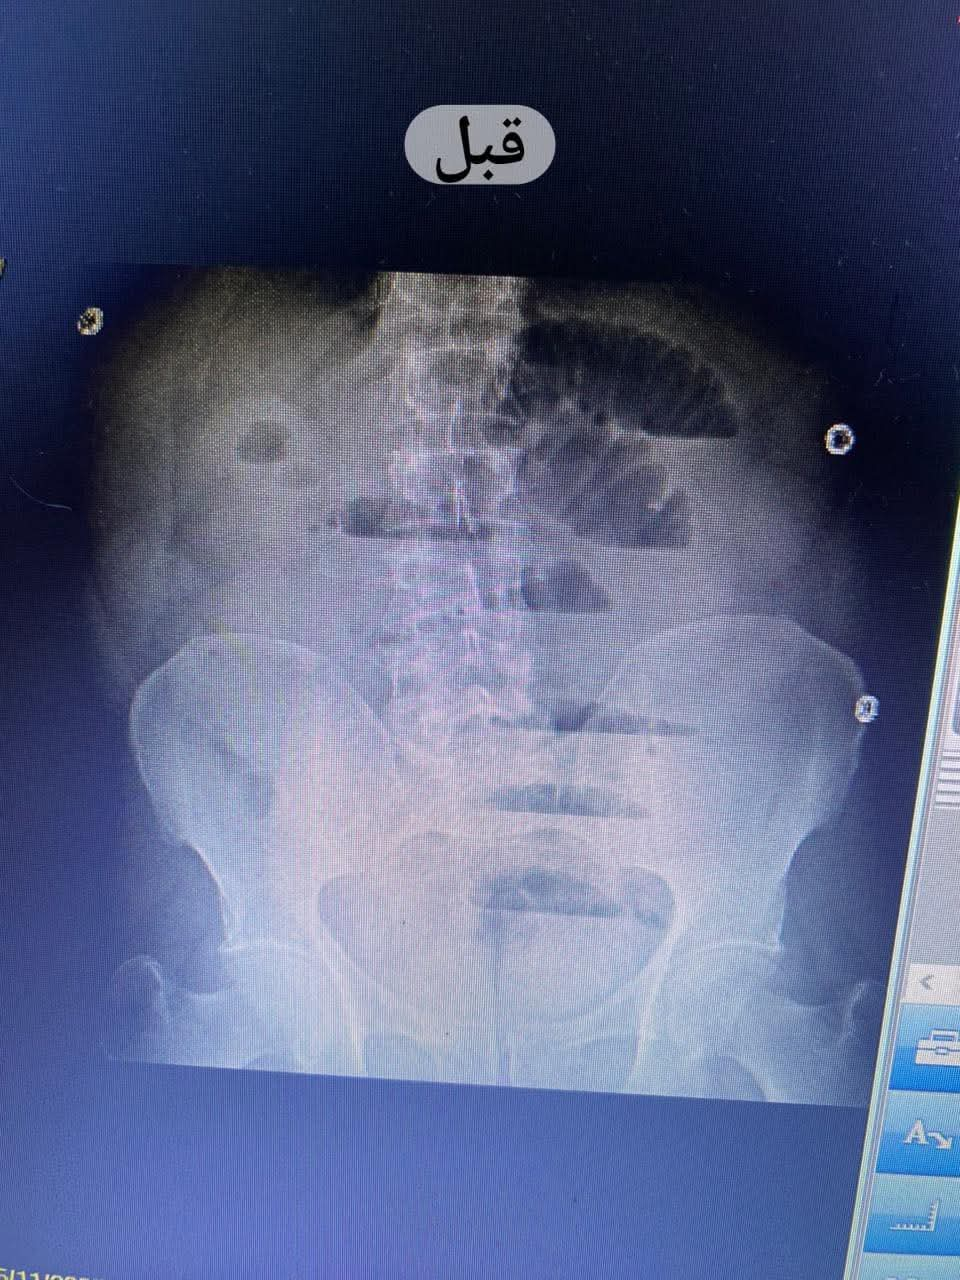

تم إجراء الفحوصات اللازمة حيث أظهرت الأشعة التليفزيونية والعادية على البطن وجود انسداد معوي كامل ناتج عن اختناق الأمعاء داخل كيس الفتق؛ ما استدعى سرعة تجهيز المريض لغرفة العمليات وإجراء عملية استكشاف للبطن على وجه السرعة وفقا للبروتوكولات العلاجية المعتمدة.